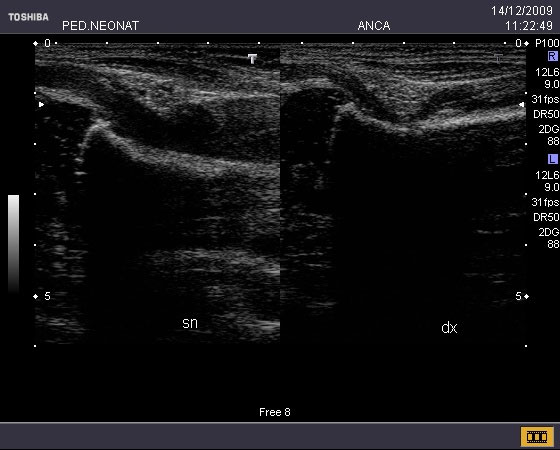

Al ricovero, appare evidente anche una tumefazione rosea ma non calda che interessa la parte prossimale dello stesso arto (Figura 1 e Figura 2). Tutto sommato, per�, la piccola non sembra avere un aspetto particolarmente sofferente: il suo colorito � roseo, non presenta febbre, i parametri vitali sono nella norma, si alimenta bene e non ha perso peso rispetto ai giorni precedenti. Viene eseguita una Radiografia del bacino che esclude lesioni ossee ma evidenzia uno �slargamento dello spazio articolare coxo-femorale a sinistra associato a una fine disomogeneit� strutturale dell�epifisi prossimale del femore omolateralmente�, quadro radiologico tipicamente associato a Osteo-Artrite Settica. Viene subito praticata un�ecografia delle anche dalla quale emerge la presenza di �versamento articolare a sinistra che distende la capsula, a ecostruttura disomogeneamente ipooecogena; la muscolatura periarticolare appare lievemente ipoecogena rispetto all�arto contro laterale; � inoltre presente ipervascolarit� al color doppler� (Figura 3).

Figura 3. Ecografia comparativa in cui si apprezza un notevole versamento articolare a sn che distende la capsula, rispetto all�articolazione normale a dx